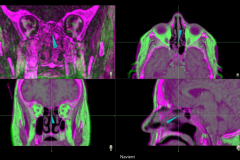

Navient Neuronavigation System

Cranial, Biopsy, Spine, ENT

Software

• Import Dicom images from DVD, USB and PACS

• Fast and accurate image fusion

• Automatic detection of fiducials for registration

• Anatomical landmark registration

• Trace registration

• Biopsy trajectory planning and navigation

• Virtual tip extension

• Axial, coronal, sagittal, and 3D probe’s eye view

• Easy manipulation of 2D and 3D images

• Video documentation of surgical operation

• Warnings issued if line of sight interrupted

• Gesture based user interface control

• Smart Zoom magnifies navigation area

• Instrument tip accuracy verification

• Remote support and software update